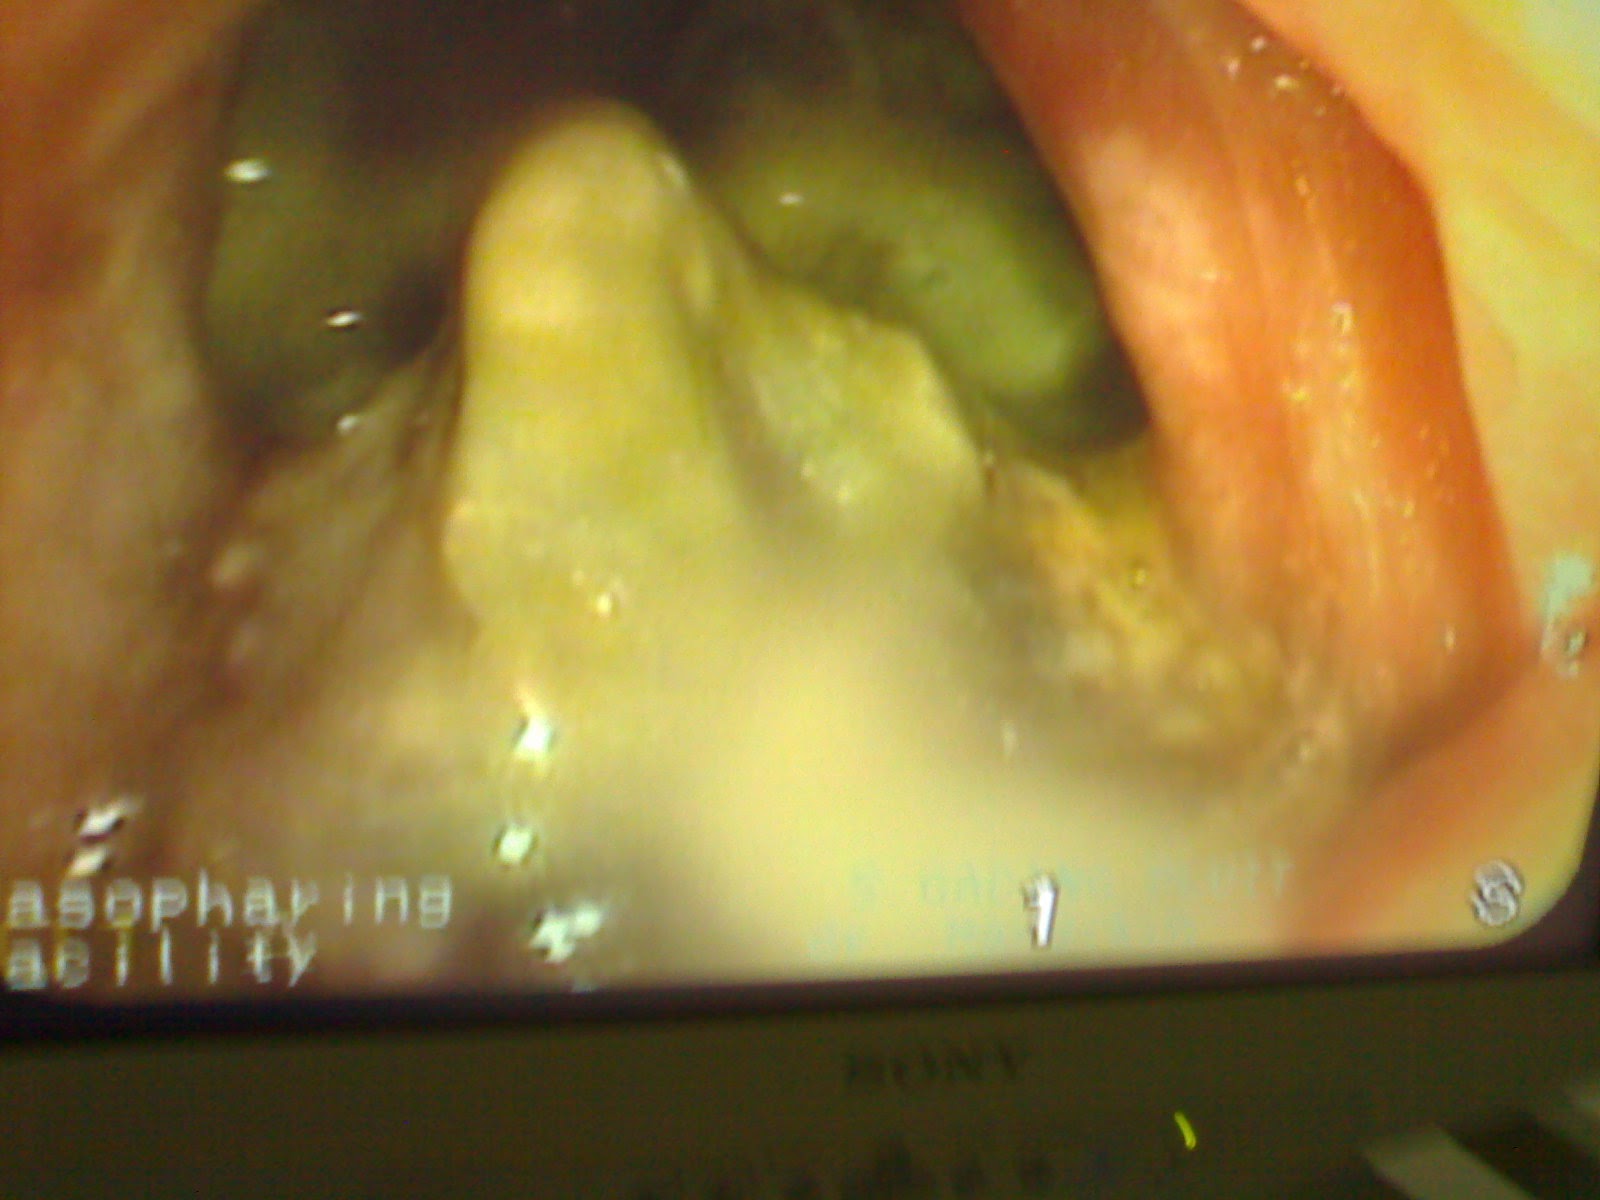

Diagnosis

pasti ditegakkan dengan melakukan biopsi nasofaring. Biopsi dapat dilakukan

dengan 2 cara dari hidung atau dari mulut.

- Biopsi melalui hidung dilakukan tanpa melihat

jelas tumornya (blind biopsy). Cunam biopsi ini dimasukkan melalui rongga

hidung menyelusuri konka media ke nasofaring kemudian cunam diarahkan ke

lateral dan dilakukan biopsi.

- Biopsi melalui mulut dilakukan dengan

menggunakan kateter nelaton yang dimasukkan melalui hidung dan ujung kateter

yang berada dalam mulut ditarik ke luar dan diklem bersama-sama ujung kateter

dan hidung disebelahnya, sehingga palatum mole tertarik ke atas. Kemudian

dengan kaca laring dilihat daerah nasofaring. Biopsi dilakukan dengan melihat

tumor melalui kaca tersebut atau memakai nasofaringoskop yang dimasukkan

melalui mulut, massa tumor akan terlihat dengan jelas. Biopsi tumor

nasofaring umumnya dilakukan dengan anastesi topikal dengan xylocain 10%.